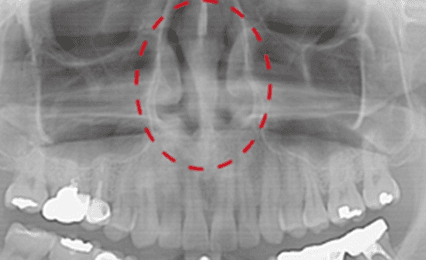

하악 전진을 통한 기도 확보 메커니즘

파사는 수면 중 하악을 전방 위치로 유도함으로써 혀의 후방 이동과 연조직 붕괴를 감소시키고, 상기도 공간 확보를 돕는 MAD(Mandibular Advancement Device)입니다.

- 하악 전진 → 혀 기저부 전방 이동

- 연구개·연조직의 후방 처짐 감소

- 수면 중 기도 저항 감소에 기여